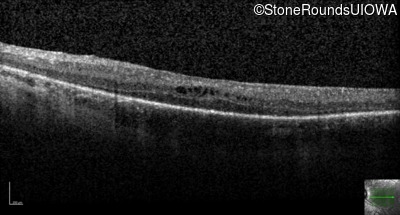

Optical Coherence Tomography - Right - 20/40

Exemplar / OCT Stack